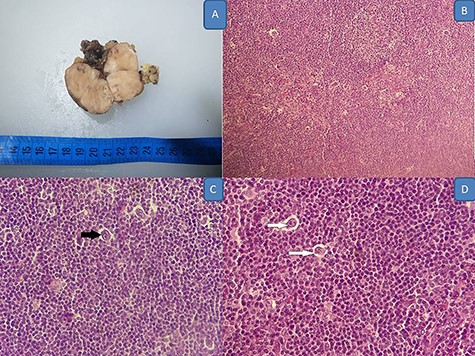

A 20-year-old woman with no medical history presented with a 4-month history of paresthesia in her right ulnar nerve’s sensory territory, and swelling in the cubital fossa 5 weeks before consulting. On examination, she was a healthy woman with stable vital signs; there was a painful tender mass in the cubital fossa (Fig. 1A). Magnetic resonance imaging (MRI) revealed an intraneural well demarcated tumor, measuring 4.8 × 2.7 × 2.5 cm, which was hypointense on T1- and T2-weighted images (Fig. 1B). The interpretation was that of a benign tumor more likely a schwannoma. Thus, a biopsy was performed. On histology, Hematoxylin–eosin stained sections revealed a tumor consisting of sparse large mononuclear cells, with thick nuclear membrane and large nucleoli. Typical multinucleated Reed Sternberg cells and lacunar were also observed. The inflammatory background was dense; composed of plasma cells, neutrophils, eosinophils, histiocytes and small lymphocytes. The latter arranged, in some areas, in primary lymphoid folliculs with germinatif center. On immunohistochemistry, neoplastic cells expressed CD30, CD15 and Pax5 and were negative for CD20 and CD3. The patient underwent surgical excision of the mass. On gross, it was a well demarcated spherical mass measuring 4.2 × 2.5 cm with withe to gray cut surface. The texture was firm at sectioning (Fig. 2A). Morphological and immunohistochemical studies confirmed the diagnosis (Figs 2 and 3). Examination confirmed the diagnosis of classical Hodgkin lymphoma. Physical examination and thoraco abdominal pelvic CT scan failed to show any evidence of generalized lymphoma; bone marrow biopsy was also negative. In the absence of either lymph nodes or extranodal involvement, the diagnosis of primary ulnar nerve HL was retained. The patient was referred to hematology department. Two months later the patient presented with cervical adenopathy, histological examination was consistent of HL. Chemotherapy treatment was initiated.

(A) Gross appearance of the mass; (B–D) Hodgkin lymphoma’s histology: neoplastic cells within a reactive inflammatory background: B (HE, x20O), C (HE X 400 black arrow showing RSB cell) and D (HE, X 400 white arrows showing Hodgkin cell).